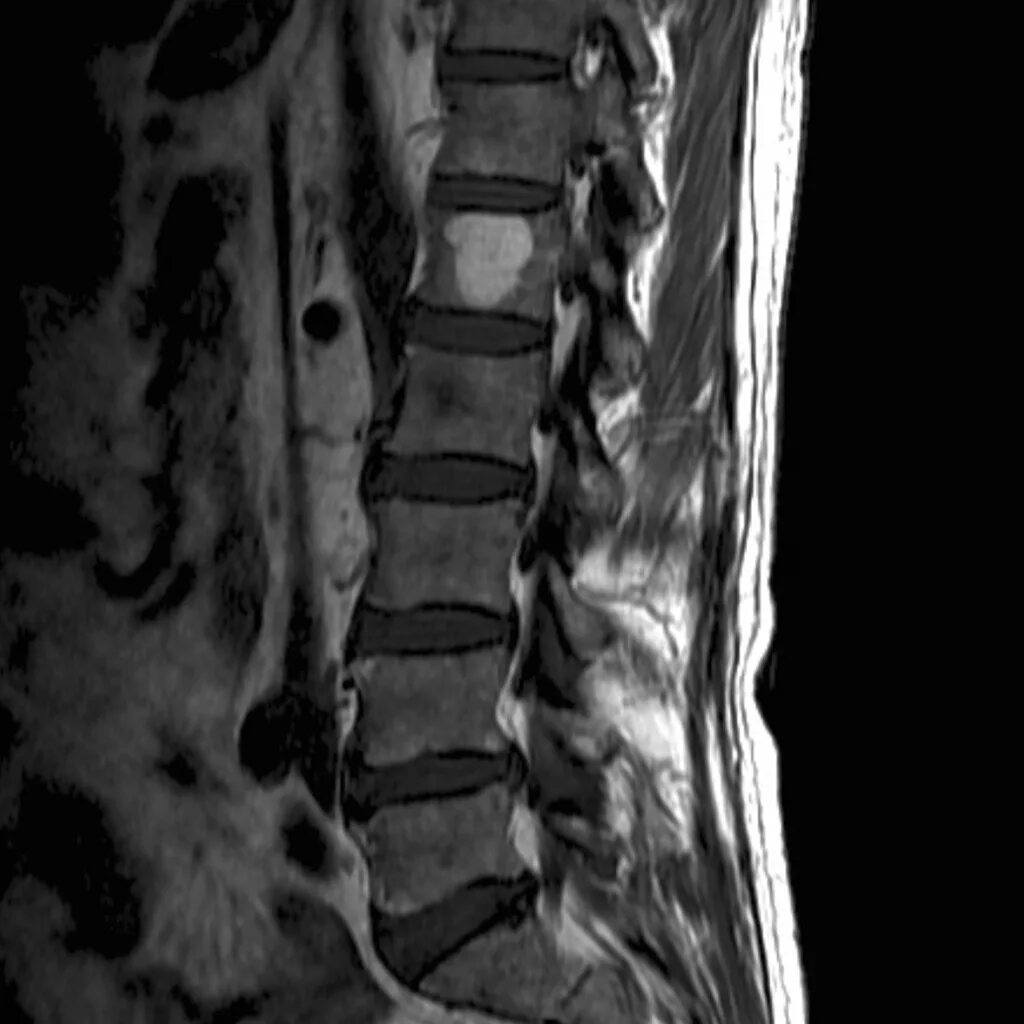

Мрт шейно поясничного отдела